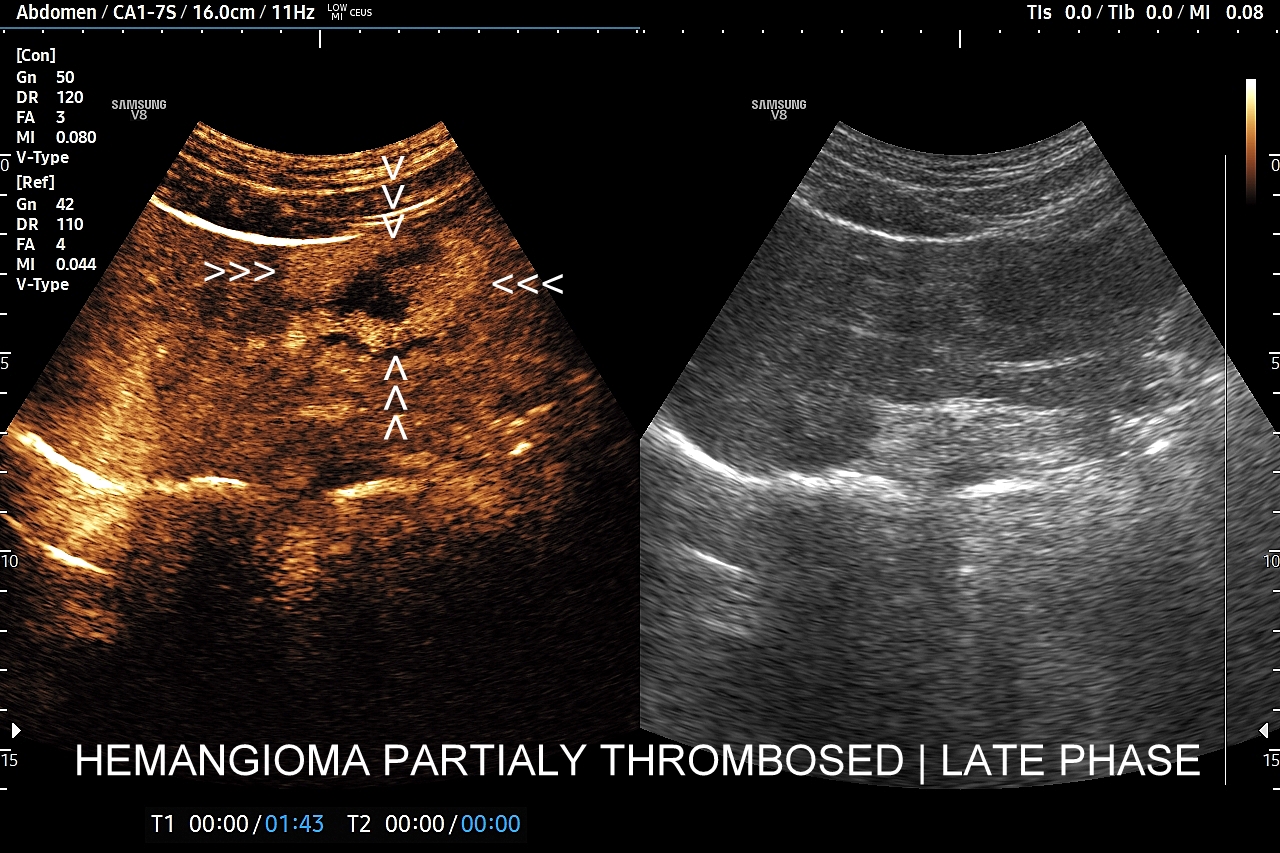

Najbardziej charakterystyczną cechą naczyniaka wątroby w badaniu CEUS jest jego wypełnianie w postaci guzkowej (ang. peripheral nodular enhancement) od obwodu ku centrum zmiany (ang. centripetal). Szybkość wypełniania bywa różnorodna, może być powolna lub szybka. W przypadku szybkiego wypełniania (tzw. flash-filling), w celu wykazania charakterystycznego centrypetalnego wypełniania niezbędna może być postprocessing’owa analiza poklatkowa zapisanego nagrania badania. W fazie późnej naczyniak wątroby pozostaje izowzmocniony lub hyperwzmocniony w stosunku do natywnego miąższu wątroby.

W przypadku dużych naczyniaków obszary, które uległy wykrzepianiu pozostają awaskularne przez wszystkie fazy badania CEUS, tj. nie wypełniają się kontrastem (nonenhancing). W przeciwieństwie do powyższego konstelacja, w której to w fazie wczesnej pojawia się wzmocnienie, a następnie w fazie wrotnej lub późnej ulega wypłukaniu (hypoenhancement) świadczy o cechach złośliwych diagnozowanej zmiany ogniskowej w wątrobie i wyklucza rozpoznanie naczyniaka.